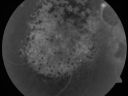

Pigmented Choroidal Mass Right Eye - Melanoma vs. Nevus vs. Unilateral Melanocytic Proliferation - 4 Month Follow-Up Images692 views71-year-old man his vision 4 month follow-up. Vision is 20/60 and patient sees flashing lights. Lesion has grown slightly in the superior half of the macula.     (0 votes)

PHOTOGRAPHS: Photos confirm clinical findings.

FLUORESCEIN ANGIOGRAPHY: The right eye shows hyperfluorescence corresponding to a window defect overlying the nevus. The choroidal vasculature can be easily seen throughout the area in a dependent fashion, suggestive of chronic subretinal fluid. There is also hyperfluorescence inferior to the optic nerve with hypofluorescence over the area of geographic atrophy. There is some stippled hyperfluorescence within the lesion in the late frame. The hyperfluorescence in general fades in the late frames. There is no evidence of any active leakage. The drusen over the surface of the nevus inferonasal to the optic nerve, which is overall dark, do stain in the late frames as well. The left eye is angiographically normal throughout the studies.